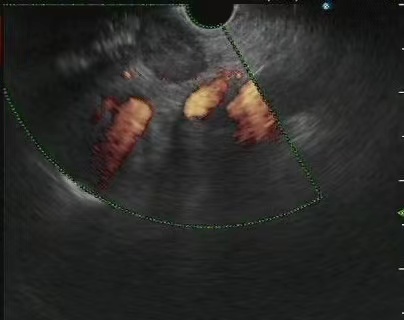

胃体淋巴瘤超声内镜检查并深挖活检4、胰腺疾病的诊断超声内镜扫查胰腺实质,可以发现B超和CT无法发现的微小病变,还可以对病灶部位进行超声内镜引导下细针穿刺活检(EUS-FNA)。除了肿瘤本身,对周围淋巴结、器官的扫描可以辅助疾病分期。

胰腺占位EUS-FNA